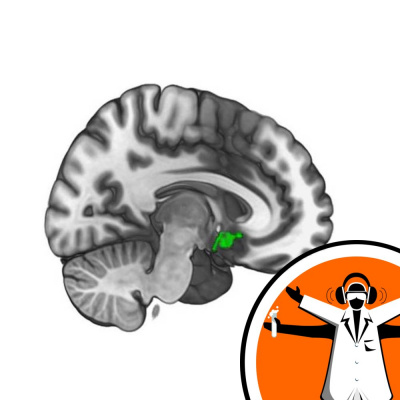

Although empathy is often associated with traits like helpfulness and generosity, not a lot is known about how helpful behaviour and empathy might be linked in the brain. Now, scientists have pinpointed part of the brain thought to drive us to learn how to be more helpful. The findings also suggest that people with higher levels of empathy are quicker to learn what they need to do to help. Patricia Lockwood and her team measured participants' brain activity in an MRI scanner while they tried to win money - either for themselves, or for another person, as she explained to Laura Brooks... Like this podcast? Please help us by supporting the Naked Scientists